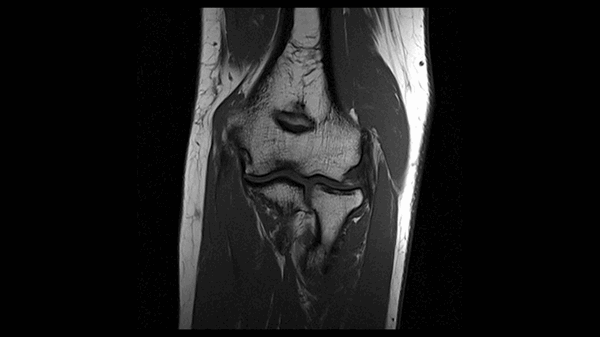

МРТ локтевого сустава в корональной плоскости. В подкожно-жировой клетчатке локтевого сустава отмечаются множественные образования неправильной вытянутой формы, местами сливающиеся между собой — вероятно, венозная мальформация.